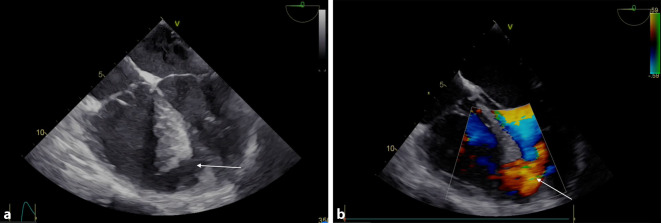

Um 2.02 Uhr wird die Schockraum-CT-Diagnostik durchgeführt, welche einen Hämatopneumothorax links ohne Spannungszeichen bei korrekt liegender Bülau-Drainage ergibt. Weiters finden sich bilateral Lungenkontusionen. Das CCT und Abdomen-CT zeigen einen unauffälligen Befund. Nach der CT-Untersuchung wird der Patient bei systolischem Blutdruckabfall auf 40 mm Hg wieder reanimationsbedürftig (Adrenalingabe und Herzdruckmassage). Aufgrund des thorakalen Verletzungsmusters ist eine echokardiographische Evaluierung lediglich subxiphoidal möglich, die Schallqualität auch von diesem Anlotungspunkt nicht zufriedenstellend. Es kann aber trotzdem (ebenfalls wie in der CT) ein Perikarderguss ausgeschlossen werden. Die Pumpfunktion des linken Ventrikels imponiert gut; der rechte Ventrikel scheint für das jugendliche Alter vergrößert. Daraufhin Durchführen einer transösophagealen Echokardiographie, welche einen unauffälligen Befund der Herzklappen, inklusive der Aorta ascendens, zeigt und neuerlich einen negativen Befund hinsichtlich eines Perikardergusses. Im midösophagealen Vierkammerblick zeigt sich aber apexnah eine Strukturunterbrechung des interventrikulären Septums und mittels Colour-Doppler ein ausgeprägter Links-rechts-Shunt (Abb. 1 und Videos im Zusatzmaterial online).

Nach Diagnosestellung einer traumatischen Ventrikelseptumruptur wird der diensthabende Kardiochirurg hinzugezogen (Abb. 2a). Parallel dazu wird durch Rücksprache mit der interventionellen kardiologischen Abteilung die Option einer Akutversorgung der Ventrikelseptumruptur ausgeschlossen. Die hämodynamische Instabilität mit insgesamt 5 Phasen der mechanischen Reanimationspflichtigkeit zwingt zum unmittelbaren Handeln und zur Indikationsstellung einer chirurgischen Sanierung unter extrakorporalem Kreislauf und Vollheparinisierung. Nach Transferierung in den durch Lift unmittelbar mit dem Schockraum verbundenen kardiochirurgischen OP werden primär unter intermittierender CPR die linken Leistengefäße kanüliert, und der extrakorporale Kreislauf wird um 3.40 Uhr begonnen. Danach erfolgen die Thorakotomie und aufgrund inadäquater Blutflüsse über die inguinalen Kanülen eine zentrale Kanülierung. Die chirurgische Sanierung erfolgt über einen rechtsventrikulären Zugang in Form eines Patch aus Rinderperikard, welcher mit Prolen-Einzelkopfnähten und Plegets fixiert wird. Intraoperativ entwickelt der Patient eine weite entrundete lichtstarre Pupille links bei adäquatem Perfusionsdruck, welche sich am Ende der Operation wieder zurückbildet. Nach Öffnen der Aortenklemme weist der Patient biventrikulär eine unzureichende Pumpleistung mit Low-cardiac-output-Syndrom auf, welches aus unserer Sicht multifaktoriell bedingt ist: Sichtbares Hämatom in Vorderwand und Ausflusstrakt des linken Ventrikels, chirurgische Inzision des rechten Ventrikels und generalisiertes myokardiales Kontusionstrauma. Weiters kommt es mehrmals zu massiv blutig schaumiger Sekretion aus dem Endotrachealtubus mit konsekutiver insuffizienter Beatmung. Folglich wird für die postoperative Betreuung eine zentrale venoarterielle ECMO installiert. Im Anschluss erfolgt die unfallchirurgische Versorgung des Amputationsstumpfes und der Weichteilverletzungen sowie augenchirurgisch bei Bulbusruptur die Enukleation des rechten Auges. Die operative Versorgung nimmt insgesamt 10 h in Anspruch, danach wird der Patient intensivmedizinisch betreut.